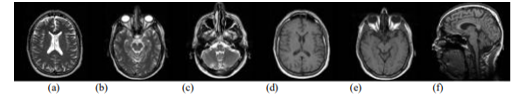

Figure 2 : MRI of brain cited by http://www.mr-tip.com/serv1.php?type=isimg. T2 weighted MR image (a) brain shows cortex, lateral ventricle, and falx cerebri, (b) brain shows eyeballs with optic nerve, medulla, vermis, and temporal lobes with hippocampal regions, (c) head shows maxillary sinus, nasal septum, clivus, inner ear, medulla, and cerebellum. T1 weighted MR image (d) brain shows cortex, white and grey matter, third and lateral venticles, putamen, frontal sinus and superior sagittal sinus, (e) brain shows eyeballs with optic nerve, medulla, vermis, and temporal lobes with hippocampal regions,(f) brain shows cortex with white and grey matter, corpus callosum, lateral ventricle, thalamus, pons and cerebellum from the same patients